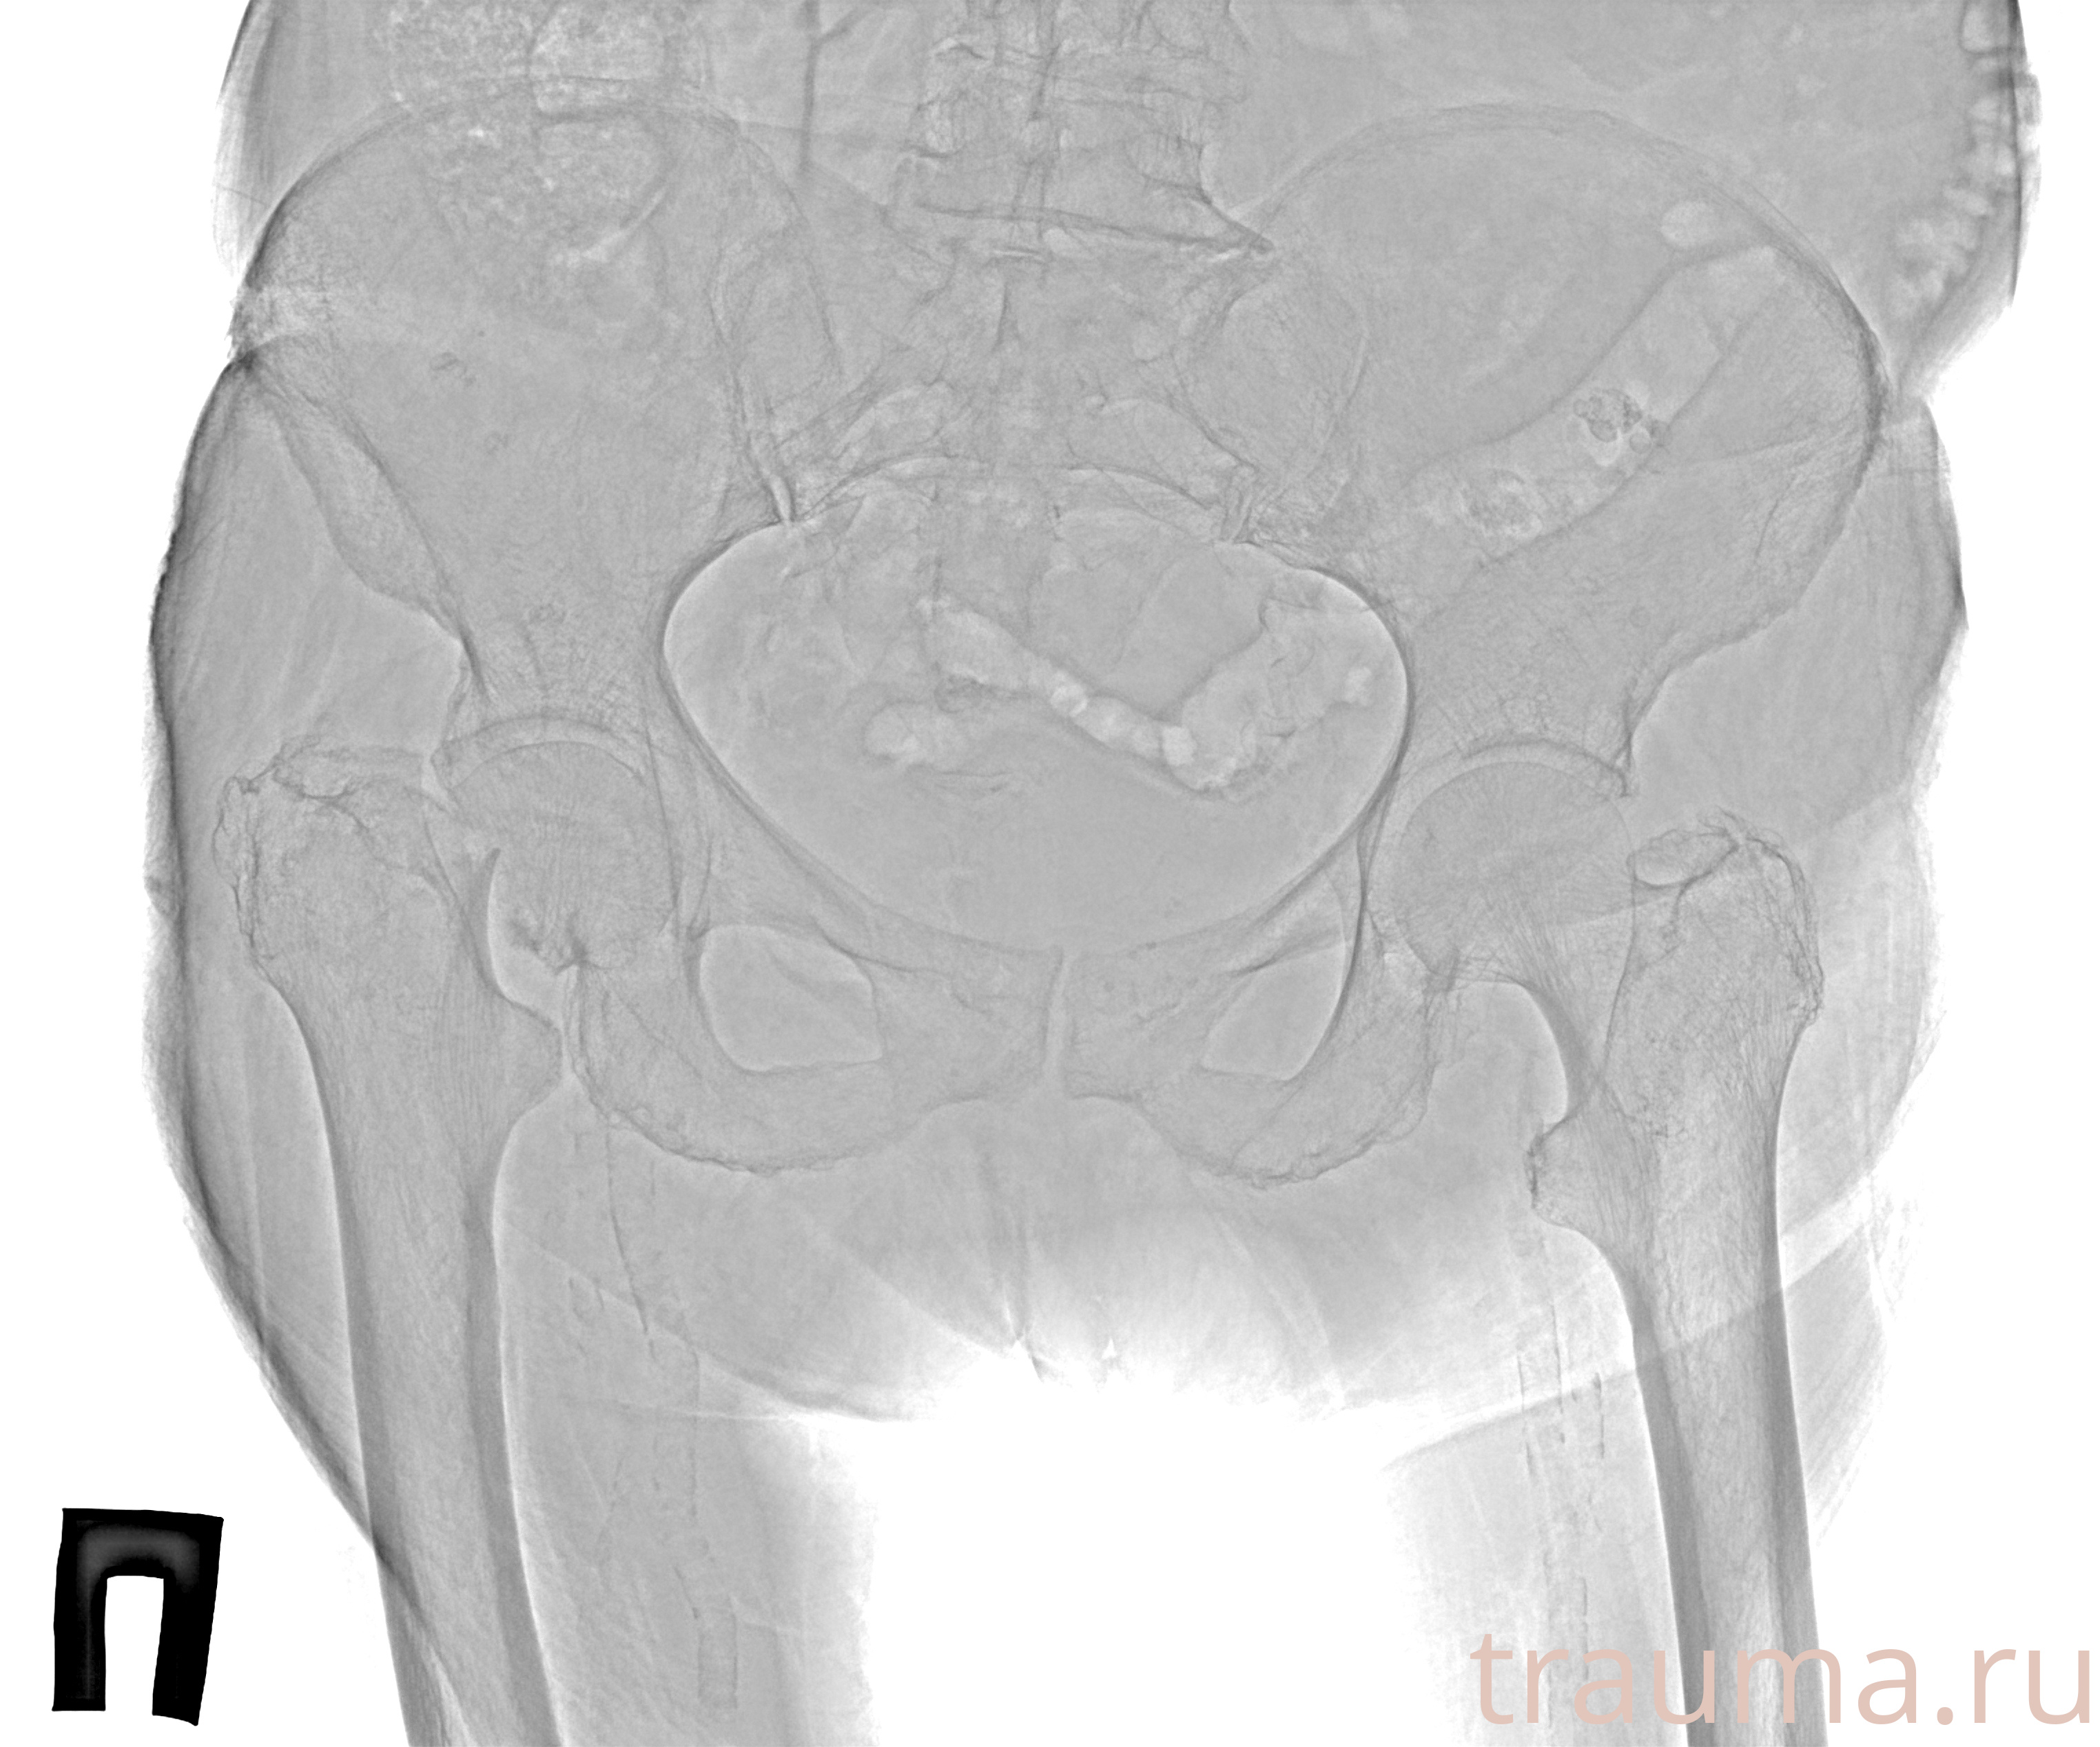

Рентгенограммы

Рентген на дому: по вашему адресу приезжает врач-рентгенолог, травматолог-ортопед с мобильным рентгеновским аппаратом, проводит диагностику травмы или заболевания, делает необходимые рентгенограммы, дает рекомендации по дальнейшему лечению. Получить качественные снимки в домашних условиях возможно благодаря уникальной методике, разработанной МосРентген Центром для института  Склифосовского